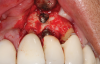

This is where the treatment became challenging. First, a curette was used to attempt to remove the granulation tissue from around the apex of the implant circumferentially. This was a difficult endeavor, especially on the palatal aspect of the site. Following curettage, an 810 nm diode laser (NV® PRO3, DenMat [alternatively: Picasso+, AMD Lasers; Gemini, Ultradent]) was used to treat the apical portion of the implant. After the laser tip was initiated using dark occlusal paper (Figure 4), it was used to debride the remaining necrotic tissue and decontaminate the entire site, reducing the bacterial count (Figure 5 and Figure 6).

(4.) The diode laser tip was initiated with dark blue occlusal paper.

Figure 4

(5.) The physical granulation tissue was ablated, and the entire site was decontaminated, reducing the bacterial count.

Figure 5

(6.) View of the cleaned site ready to be repaired.

Figure 6